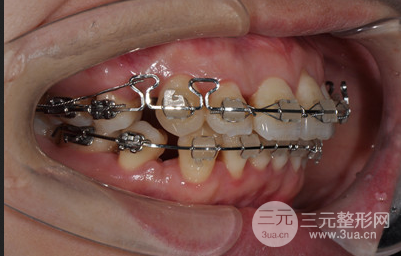

在做牙齒正畸這段時間里,一直都堅持飲食清淡和清潔工作,不能過度咀嚼,所以在著兩年多的堅持下還是有很明X的改良的。

矯正期間沒個一段時間就要回醫(yī)院做復(fù)查和更換牙套,好在醫(yī)生的技術(shù)比較好,牙齒矯正比較爭氣,現(xiàn)在想過很滿意,不僅沒有凸嘴,牙齒也很整齊,現(xiàn)在已經(jīng)取了牙套之后可以隨意吃吃喝喝了,這兩天沒有白堅持。